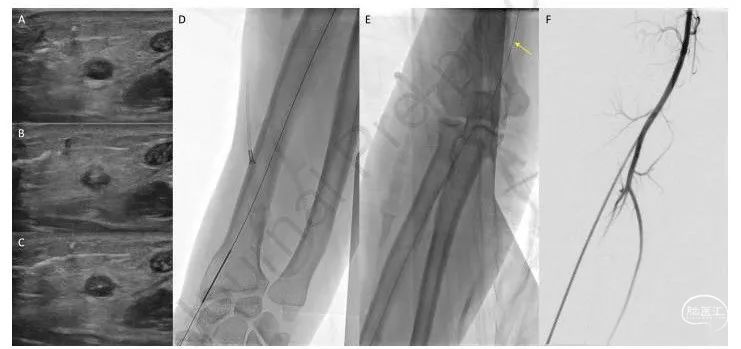

图2.成功放置经桡动脉鞘的桡动脉闭塞患者示例。使用超声识别闭塞的桡动脉(A),该动脉不会搏动并且缺乏彩色多普勒信号,但必须进行测量以确认其足够大以容纳所需的鞘。使用单壁21g穿刺针在与传统桡动脉通路相同的解剖位置刺穿血管腔(B、D)。由于在进入管腔时不会提供血液回流的反馈,因此必须在超声上清楚地看到针尖在血管腔内(B)。然后,将一根0.021英寸的微导丝穿过闭塞的动脉并进入肱动脉(C、D、E箭头)。在超声上观察血管腔内的微导丝以确认导丝通过管腔(C)。根据研究者经验,所需的鞘必须为23厘米,最大直径可达8Fr,然后将鞘通过导丝送入肱动脉,随后进行血管造影以确认鞘的正确放置(F)。